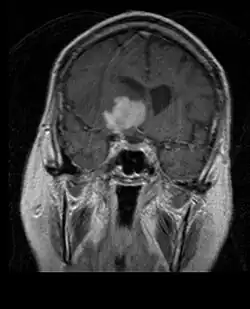

A tomografia computadorizada (TC) e a ressonância magnética (RM) podem detectar efetivamente uma neoplasia no cérebro. A RM é mais sensível que a TC para identificar lesões, mas contraindicações para pacientes com marcapasso cardíaco, próteses incompatíveis, clipes metálicos e outros. A TC continua sendo o método de escolha para detectar calcificações dentro de lesões ou erosões ósseas da calota craniana ou da base. A utilização de agentes de contraste, que são iodados no caso da TC e paramagnéticos ( gadolínio ) no caso da RM, permite a aquisição de informações sobre a vascularização e integridade da barreira hematoencefálica, uma melhor definição do tumor tumoral comparado ao edema circundante e à geração de hipóteses sobre o grau de malignidade . O exame radiológico também permite avaliar os efeitos mecânicos e consequentes alterações nas estruturas cerebrais decorrentes do tumor, como hidrocefalia e hérnias, cujos efeitos podem ser fatais. Finalmente, na preparação para a cirurgia, esse diagnóstico pode ser usado para determinar a localização da lesão ou a infiltração do tumor em áreas vitais do cérebro. Para isso, a RM é mais eficiente que a TC, pois pode fornecer imagens tridimensionais.

As ferramentas de diagnóstico por imagem radiológica destacam a mudança no tecido neoplásico em comparação com o parênquima cerebral normal (através de alterações na densidade do tecido fotografado eletronicamente na TC e na intensidade do sinal na RM). Como a maioria dos tecidos patológicos, os tumores também são reconhecidos por um acúmulo aumentado de água intracelular. Na tomografia computadorizada aparecem hipodensa, ou seja, de menor densidade que o parênquima cerebral, na tomografia de ressonância magnética nuclear com relaxamento spin-lattice T 1 hipointenso e em relaxamento spin-spin T 2 bem como a ponderação de prótons (PD) hiperintensa.

No tecido tumoral, em geral, a maior proporção de realce pelo contraste se deve à barreira hemato-tumor particular que permite a passagem de iodo (TC) e gadolínio (RM) para o espaço intersticial extravascular intratumoral. Isso aumenta o sinal (densidade ou intensidade) do tumor. No entanto, deve-se ter cuidado para garantir que o realce do contraste não diferencie definitivamente a neoplasia do edema periferida. De fato, o achado anátomo-patológico no tecido tumoral de glioma infiltrante maligno, como no glioblastoma e no astrocitoma anaplásico, também mostra além do edema vasogênico causado pela destruição da barreira hematoencefálica pelo tumor. Esta última condição clínica é pouco detectável pelo diagnóstico por imagem.

Na ressonância magnética, um tumor intracraniano aparece como uma lesão maciça que pode se tornar mais luminescente após o uso do agente de contraste. No entanto, há sempre uma anomalia de sinal na ressonância magnética, que indica a presença de neoplasia ou edema vasogênico. Normalmente, o aumento da luminescência (realce pelo contraste) é indicativo de um tumor de grau mais alto de malignidade. Um anel contrastante é característico do glioblastoma, com a porção luminescente correspondendo à parte vital do tumor maligno e a área mais escura-hipointense à necrose tecidual.